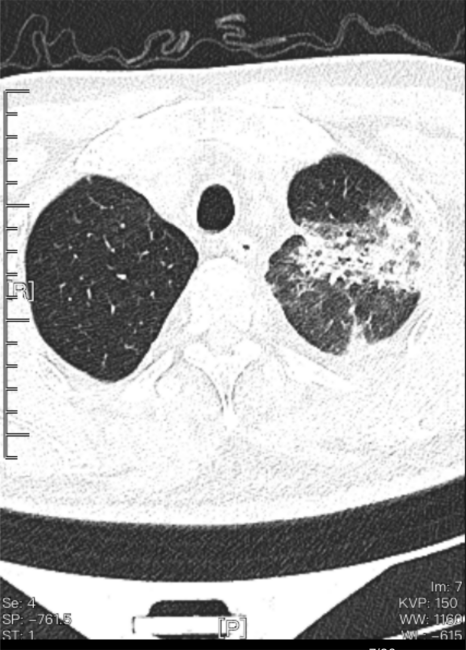

感染科医生经问诊和检查发现,诊断老人患有肺部重症感染、2型糖尿病、肾功能不全。CT检查显示肺部已有大片‘白肺’出现,说明这肯定不是普通的感冒,但蹊跷的是,流感、新冠、结核、真菌、血培养等多项检查结果均为“阴性”。

image.png入院当天胸部CT检查显示肺叶大片实变